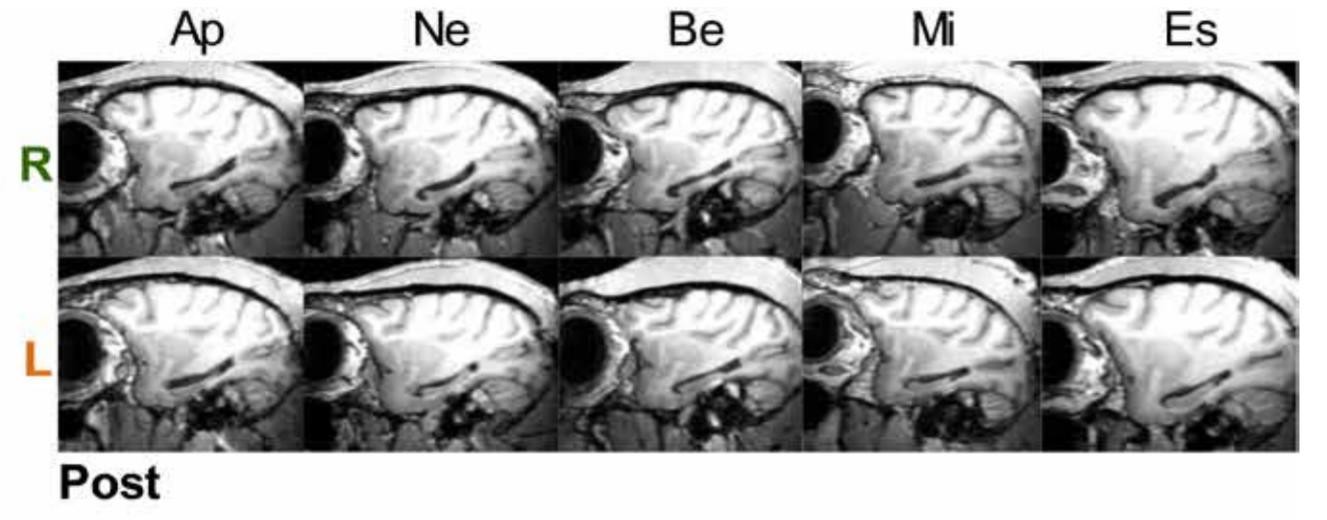

Самым известным пациентом, изучая которого ученые сделали множество выводов о роли гиппокампа, был Генри Молисон, или H.M. Борясь с эпилепсией, врачи удалили у него обе половины гиппокампа, и с тех пор он не мог запоминать новые события. H.M. умер в 2008 году, его мозг извлекли и изучили — в результате ученые подтвердили, что, кроме гиппокампа, у пациента были обширные повреждения и других зон: височной доли мозга, лобной коры, сосцевидных тел и таламуса, а также нарушена целостность белого вещества. Кроме того, оказалось, что у H.M. сохранился больший процент гиппокампа, чем считалось при его жизни.